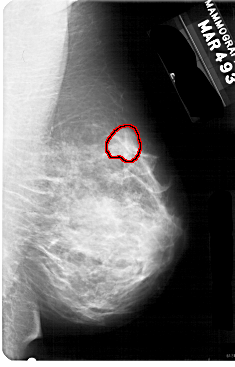

A_1752_1.LEFT_CC

RIGHT_CC LINES 5491 PIXELS_PER_LINE 3001 BITS_PER_PIXEL 12 RESOLUTION 43.5 OVERLAY

FILE: A_1752_1.RIGHT_CC.OVERLAY

TOTAL_ABNORMALITIES 1

ABNORMALITY 1

LESION_TYPE MASS SHAPE LOBULATED MARGINS OBSCURED

ASSESSMENT 4

SUBTLETY 2

PATHOLOGY BENIGN

TOTAL_OUTLINES 1

BOUNDARY